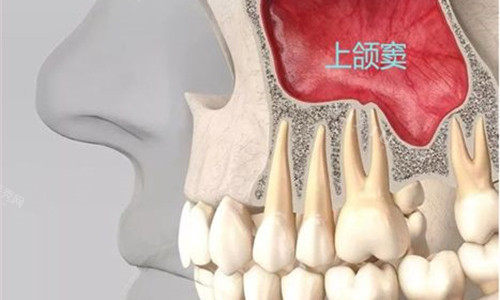

种植牙对医生技术要求较高,不妨多比较几家诊所的方案,了解所使用种植体品牌及医生相关资质。

老年人全口修复需考虑诊所是否提供超全评估和系统方案,而非单一牙齿治疗。